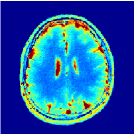

VI-E In-vivo experiments

Two sets of experiments were conducted here: first, we used the 2D and 3D acquisition sequences for scanning a healthy volunteer’s brain (real-world acquisitions). Figures 6 and 7 display the parametric maps reconstructed from 2D spiral and radial readouts. We computed the T1, T2 and proton density (PD) maps using baseline reconstruction algorithms ZF, VS, LR, FLOR, AIR-MRF and our proposed LRTV. While baselines use DM either for quantitative inference or also during reconstruction (i.e. AIR-MRF), we further compare the DM-free LRTV’s performance when cascaded to DM, KM and MRFResnet for quantitative inference. For the 3D spiral acquisitions we compared LRTV and its closest competitor VS in Figure 8. Outcomes from other tested algorithm are displayed in the supplementary materials (Figure S5). Since FLOR does not use dimensionality-reduction, our system ran out of memory during 3D reconstruction; hence results are not reported in this case.

VI-E1 Discussion

The LRTV-DM and LRTV-MRFResnet perform on par, and both outperform all tested baselines for reconstructing T1, T2 and PD maps in all acquisition schemes. This can be observed both visually in Figures 6, 7, 8, S2 and S3, and quantitatively in Table IV across all tested metrics. Other baselines were unable to successfully remove the under-sampling artefacts in TSMIs, and these errors propagated to the parameter inference phase and resulted in inaccurate maps. Temporal-only priors incorporated within LR are shown insufficient to regularise the inverse problem and LR sometimes (e.g. 2D spiral acquisitions) can admit solutions with even stronger artefacts than the model-free ZF baseline. This issue was previously studied for other non-Cartesian MRF readouts that similar to our spiral/radial trajectories, miss to sample the corners of the k-space in all timeframes (see section 2.2.2 and figure 2 in [19]). In the absence of reference for the k-space corners information, the LR iterations despite minimising the objective can converge to solutions with high-frequency artefacts, as visible in the computed maps. This highlights the need for adding an appropriate spatial-domain regularisation. FLOR reduces the LR’s artefacts but this improvement is limited because the suggested nuclear norm penalty does not incorporate an explicit spatial regularisation. Further for reducing artefacts, FLOR can introduce an undesirable bias in the computed T1/T2 maps e.g. see error maps in Figures S2 and S3. The non model-based VS baseline incorporates spatial regularisation and results in spatially smoother maps than ZF and LR, but it is unable to output artefact-free images. Further and consistent with our in-vitro experiment, we observe that VS overestimates the T2 values (e.g. in White and Grey matter regions) in tested 2D acquisitions i.e. the spatial regularisation trades off agains the quantification accuracy. The model-based AIR-MRF adds spatial regularisation through 2D/3D low-pass Gaussian filters however this trades off the sharpness of the computed maps and can increase the errors at the tissue boundaries (we searched Gaussian spreads that keep the blurs and high-frequency artefacts minimal). For our acquisition readouts, Gaussian filters performed better than disk filters of [19] for avoiding strong Gibbs artefacts. On the other hand, the spatiotemporally regularised LRTV greatly improves the TSMI reconstructions i.e. 4 dB enhancement compared to the closest competitor baseline (Table IV). This enables computing accurate and aliased-free multi-parametric inference using DM or the DM-free learning-based alternative MRFResnet as visible in Figures 6, 7, 8, S2 and S3. MRResnet and DM score competitive quantitative inference results i.e. T1 and T2 MAPE less than 5% and 9%, respectively (Table IV). KM also outputs comparably accurate T1 maps, however this shallow learning model despite having a model size larger than MRFResnet, is unable to learn accurate T2/PD quantification and it results in poor estimated maps, consistent with our observations in section VI-C.